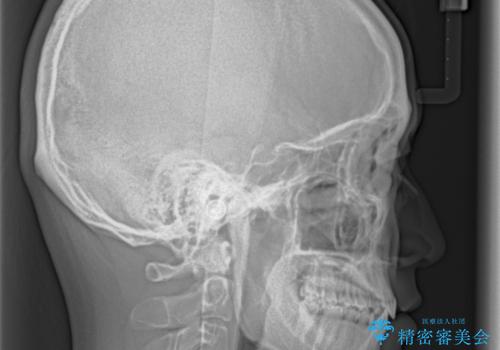

- 前歯のデコボコと隙間を気にして来院された患者様です。

治療手段としてはワイヤー装置でもインビザラインでも可能でしたが、インビザラインの自己管理は自信がないとのことで、ワイヤー矯正により隙間を閉じていくこととしました。

隙間の原因は舌の突出癖であったので、舌癖改善のためのトレーニングを指導しながら治療を進めて行くこととしました。